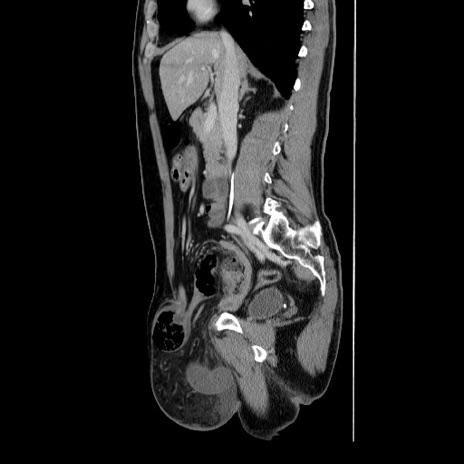

症例34(矢状断像)

【症例】60歳代 男性

【主訴】右鼠径部膨隆

【現病歴】1年程前より右鼠径部膨隆あり。自己にて還納可能だったため放置していた。3時間前より右鼠径部の脱出を認め、還納困難となり受診。

【既往歴】高血圧

【身体所見】右鼠径部に小児頭大の膨隆あり。弾性硬であり、用手還納は困難。左鼠径部にも膨隆を認める。脱出はなし。

【データ】WBC 15500、CRP 測定なし